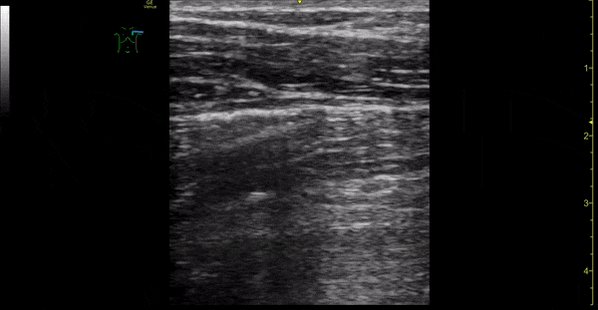

1/n #POCUS case - Pneumothorax. M/20, abrupt left pleuritic chest pain. Absent breath sound left side, hyper-resonant percussion. Absent Pleural sliding on #POCUS . No lung point found, consistent with clinical impression of large pneumothorax.

2/n Normal pleural sliding on #POCUS right anterior thorax